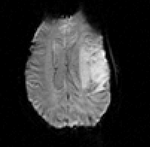

• Phase 2: Nonrigid BSpline

1. open the Registration / BRAINSfit module

1. Select Preset "Xf1_BSpline" or set the parameters as shown below:

2. fixed image: SPGR; moving image: fMRI

3. Initialize with previous transform: select the above "Xf0_Rigid"

4. Output: under Slicer BSpline Transform, select "create new" and rename to "Xf1_BSpline" or similar

5. Output: under Output Image Volume, select "create new" and rename to "fMRI_Xf1"

6. Output Image Pixel Type: check box for "ushort"

7. Registration Parameters: Number of Grid Subdivisions: 7,7,5

8. Maximum B-Spline Displacement: set to 3 [mm]

9. leave rest at defaults

10. Click: Apply

2. Return to Data module. To compare the different alignments, move the fMRI volume back under the rigid transform. BRAINSfit automatically places the moving volume into the result transform, but since nonrigid transformations cannot be visualized directly the orientation does not seem to change. For Nonrigid deformations a resampled volume must be produced to see the effect.

after non-rigid registration after additional BSpline non-rigid registration